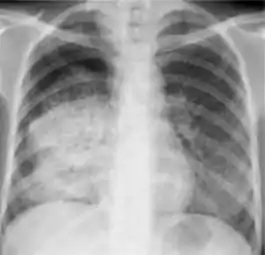

Chest x-ray of Ghon's complex of active tuberculosis